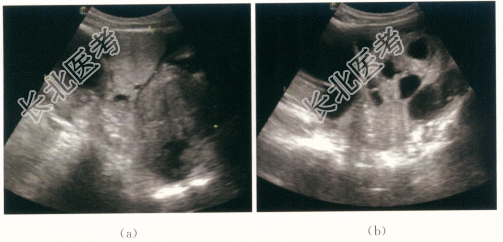

患者,女性,65岁,因“腹胀、左下腹痛伴恶心呕吐3天”就诊。患者自诉入院前3天出现腹胀、左下腹阵发性疼痛,疼痛逐渐加剧,伴恶心呕吐,呕吐后腹痛不缓解。否认头晕、发热、咳嗽咳痰、咯血、肛门坠胀感等不适。入院前一天于当地医院对症支持治疗,腹痛无明显缓解,遂至我院就诊。已绝经15年,绝经后无阴道流血流液等不适,既往月经规律,否认痛经、经量增多等不适。

患者下腹部可扪及巨大包块,上界平脐,张力大,活动度欠佳,有压痛,左侧明显,宫体触诊不清,宫颈光滑,无举痛及接触性出血。

CRP59.86mg/L,CA125100.8IU/ml,血常规、肝肾功能(-)。

- 简答题1、患者的诊断及超声依据是什么?